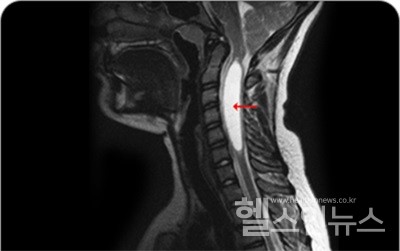

신경외과 전문의 강남베드로병원 윤강준 대표원장은 “척수공동증은 희귀 질환인 만큼 증상에 따라 최대한 꼼꼼하게 질환의 유무와 병변 부위를 파악하는 것을 최우선 목표로 해야 한다”고 설명한다. 우선 자기공명영상(MRI) 촬영, CT 촬영 등을 통해 척수 내 공동을 확인하는 것이 첫 번째다. 이에 더해 환자의 증상과 MRI에 나타나는 이상 현상의 관계를 살펴보는 과정도 함께 진행한다. 근전도 검사, 신경전도 검사, 신경계의 이상 유무를 판별하는 유발전위 검사 등을 함께 시행하기도 하며, 필요할 경우 뇌척수액 검사도 함께 시행한다.